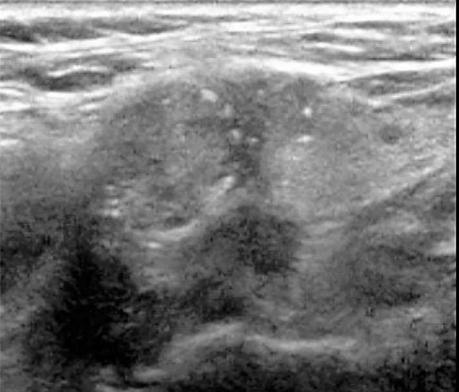

Nódulo sólido con microcalcificaciones y calcificaciones periféricas; el tumor rebasa los límites de las calcificaciones periféricas.